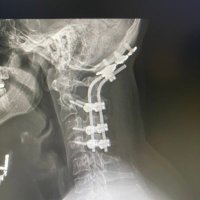

I SURVIVED BEING INTERNALLY DECAPITATED….Now I’m studying to become an engineer My life started over September 7th 2021…..I may not graduate but I will try.